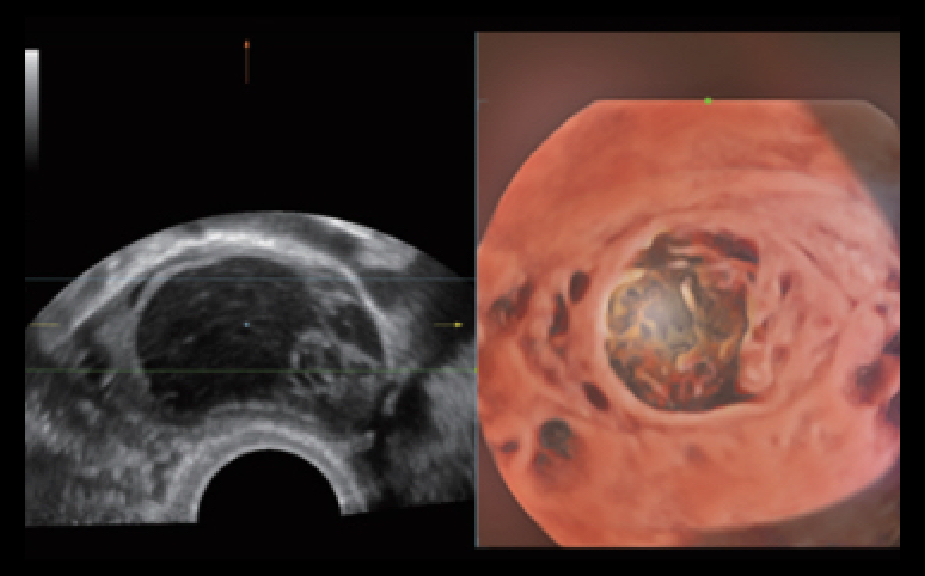

Le Nuewa?I9, con?u spÃĐcialement pour la santÃĐ de la femme et les soins nÃĐonataux, offre une expÃĐrience entiÃĻrement nouvelle gr?ce aux innovations dont il est dotÃĐ, tant à lâintÃĐrieur quâà lâextÃĐrieur. Ces innovations sont dÃĐveloppÃĐes sur la base d'une comprÃĐhension approfondie de scÃĐnarios cliniques complexes, fournissant des rÃĐponses prÃĐcises et adaptÃĐes ainsi qu'une efficacitÃĐ exceptionnelle et une expÃĐrience utilisateur remarquable.

Solution complÃĻte gr?ce au ZST +

La plate-forme ZST+?est une innovation extraordinaire, reprÃĐsentant une ÃĐvolution de lâimagerie ultrasonore. Elle transforme la formation conventionnelle de faisceaux en un traitement basÃĐ sur les canaux de donnÃĐes. Elle repousse les limites de lâimagerie conventionnelle et du compromis entre rÃĐsolution spatiale, rÃĐsolution temporelle et uniformitÃĐ tissulaire en offrant une qualitÃĐ dâimage exceptionnelle pour des solutions dâimagerie infinies et en constante ÃĐvolution.